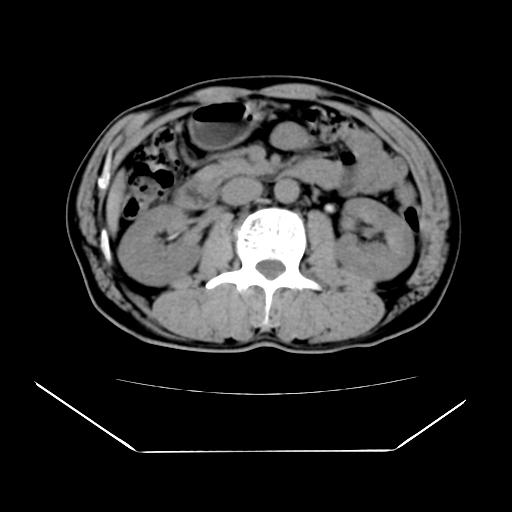

男性,55岁,外院体检afp明显升高,但b超未发现异常,否认乙肝病史。来我院ct增强。有延时扫描。

延时扫描完全充填,血管瘤

肝脏右叶动脉期可见低密度影,至延迟期被充填,考虑血管瘤可能性大。

肝右叶病灶

不排除肝右叶肝癌可能。

这个不是肝右静脉吗,这么大的病灶b超不可能发现不了吧

如果这个是癌灶的话则下腔静脉有瘤栓可能

肝6段血管瘤

血管瘤可能性大。

是肝右静脉吧

考虑肝右静脉影。